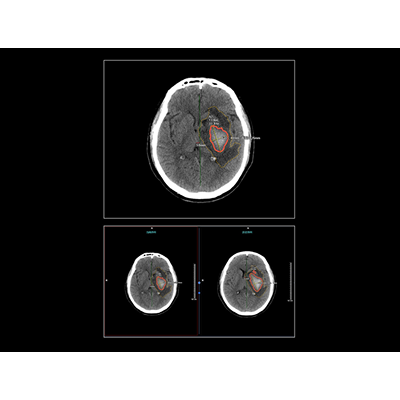

病例展示

一位61岁的男性患者因持续的头晕、头痛症状入院。而其头颅CT影像中一个微小的病灶却让当值阅片医生一时难以判断是出血还是钙化。如果将轻微出血误判为钙化灶,将极有可能导致患者病情延误,后果不堪设想。通过联影智能CT颅内出血智能分析与随访系统对患者图像进行深入分析,AI鉴别出这是脑内的出血情况,同时将其与CT影像图中微小的、易混淆的钙化灶进行了区分。这一准确的诊断为医生提供了重要的参考,他们紧急采取了针对出血的救治方法,避免了误诊和延误。